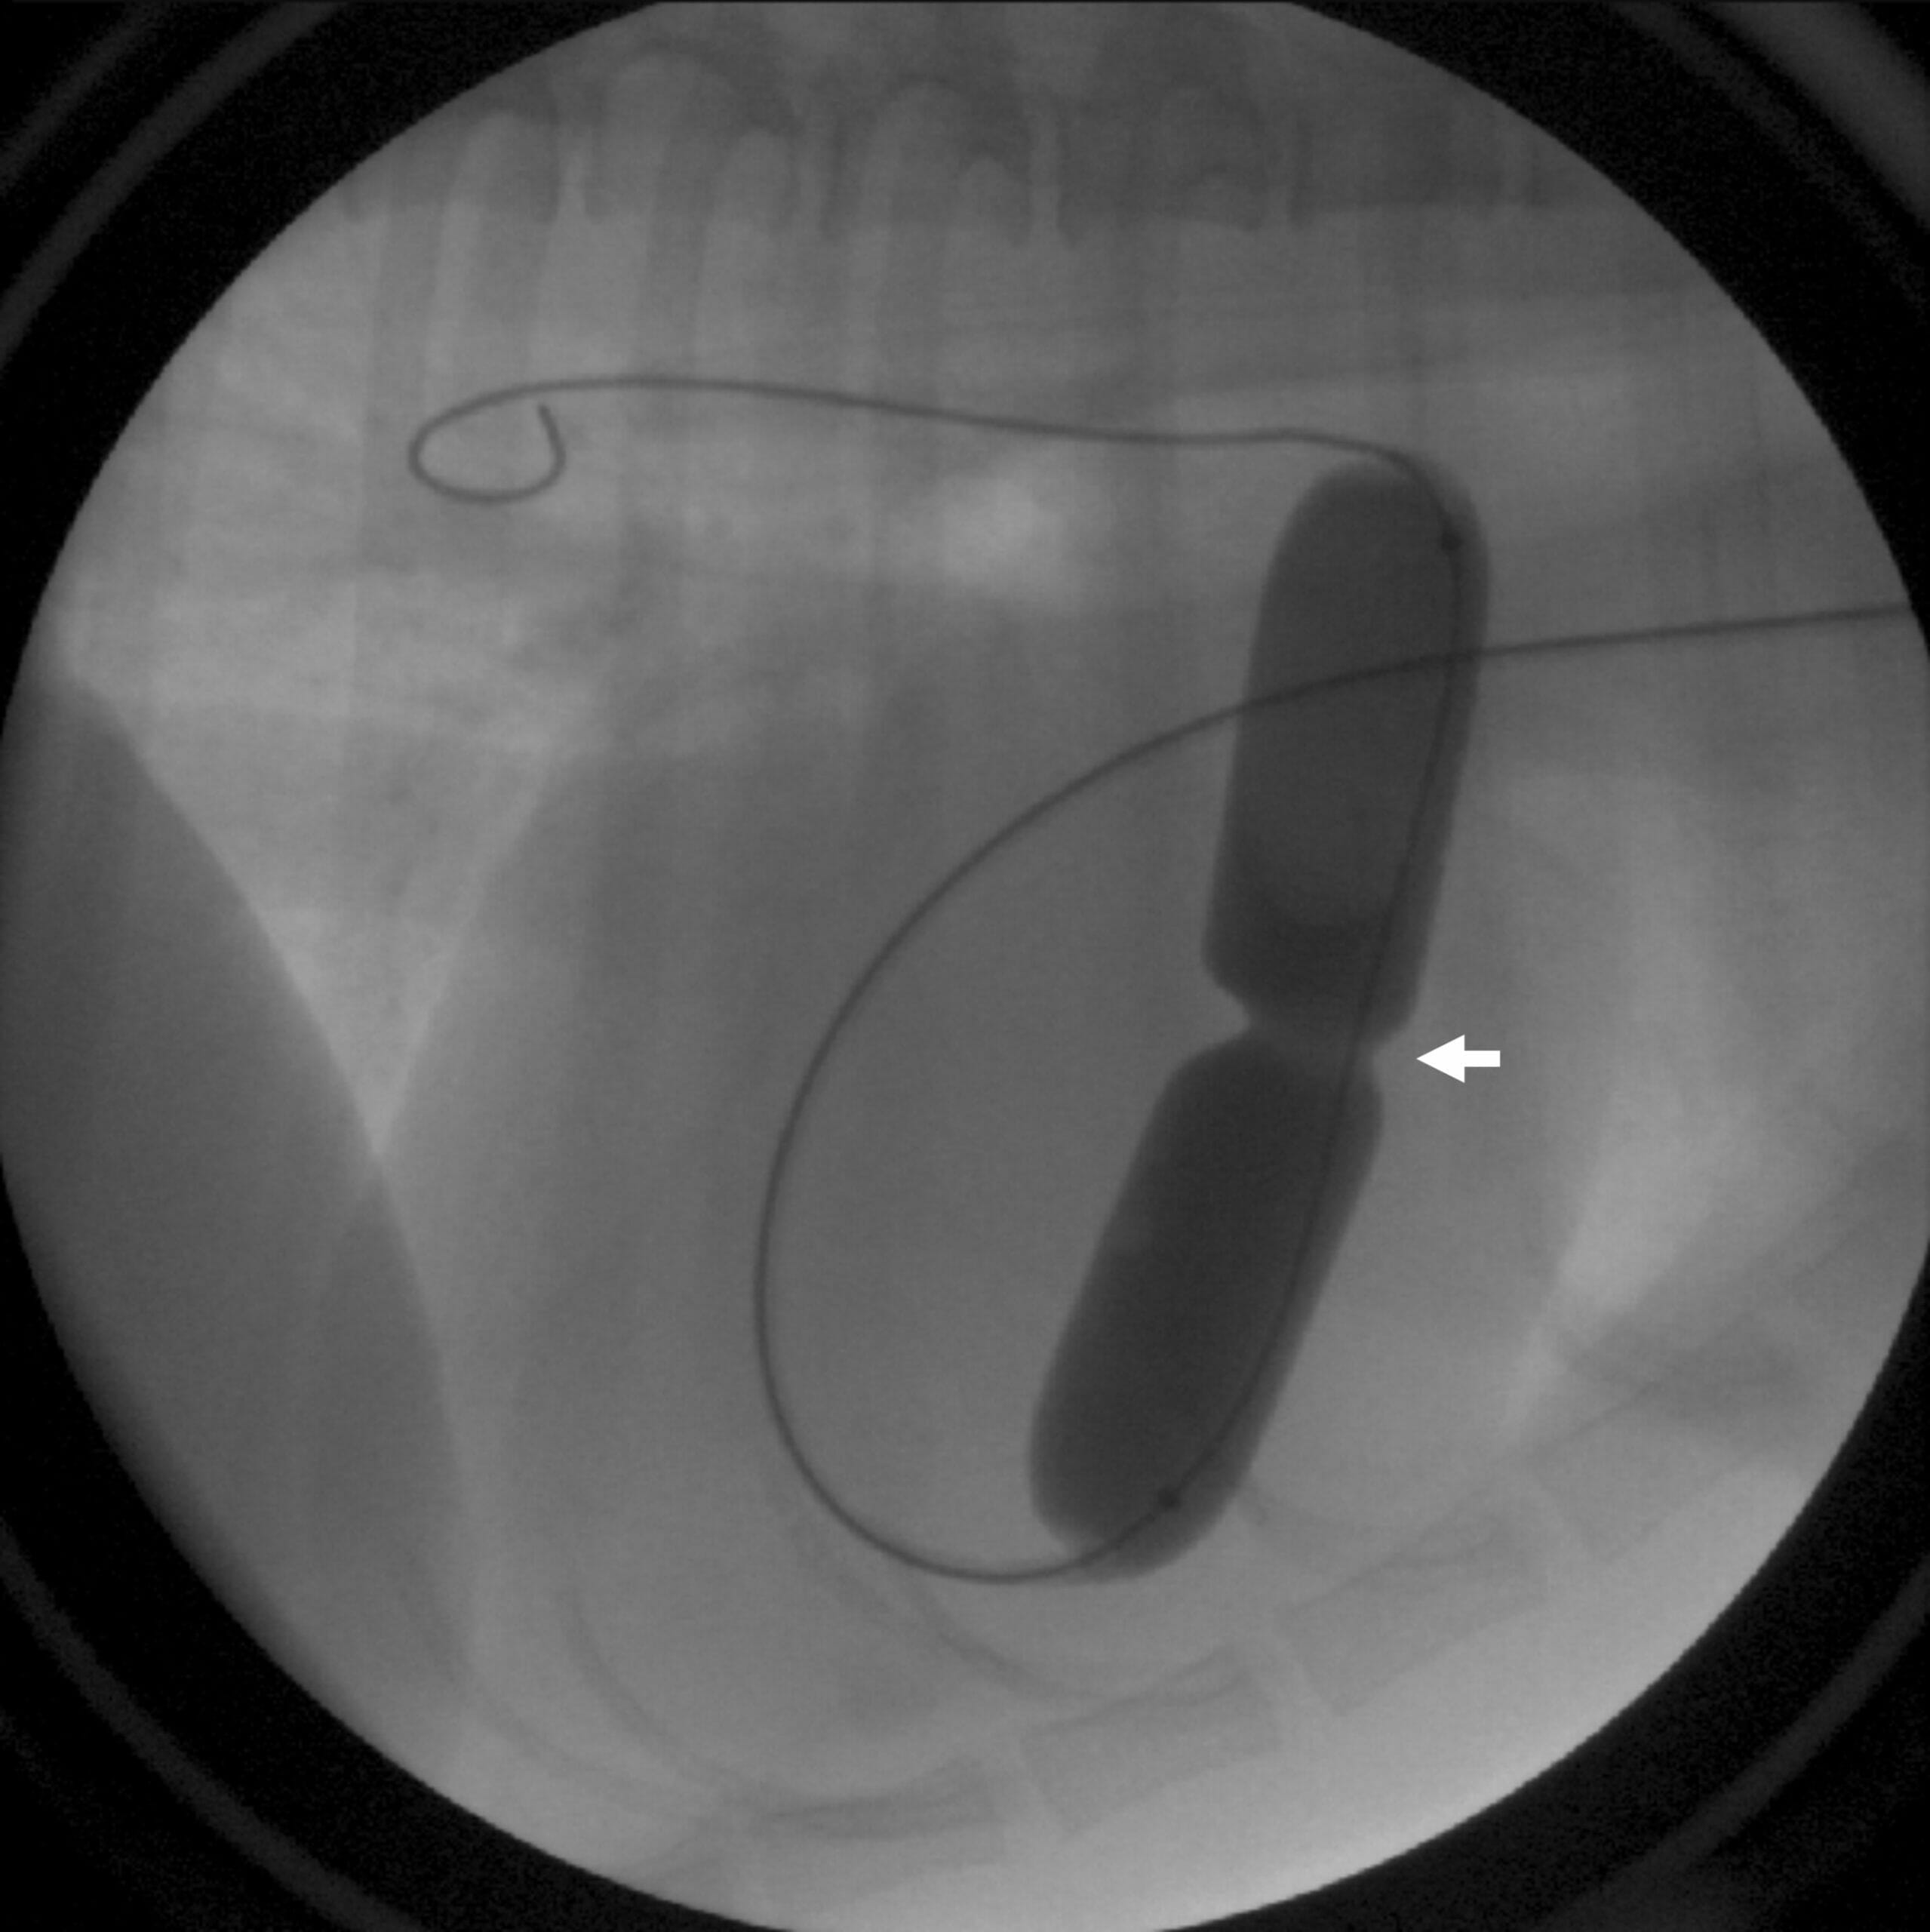

- Fluoroscopy: This real-time imaging technique allows the veterinarian to observe the trachea as your dog breathes, helping them determine the exact location and severity of the tracheal collapse.

- Surgical Intervention: In severe cases of tracheal collapse, surgery may be necessary. There are various surgical procedures available, including the placement of a stent inside the trachea to provide support and prevent collapse. Another option involves surgically attaching plastic rings to the external surface of the trachea to maintain its rigidity and shape. Your veterinary surgeon and veterinary internist will discuss the surgical options and recommend the most suitable approach for your pet.